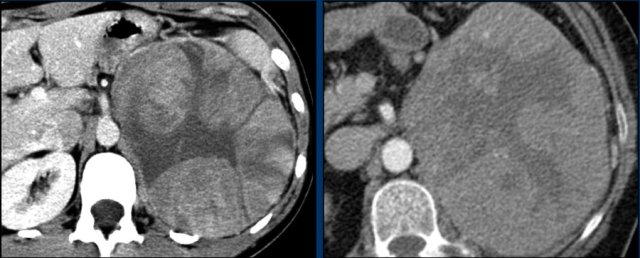

The images show an indeterminate lesion on the nonenhanced CT (density 24 HU).

The absolute washout in this patient is 62%.

This means that the lesion is a lipid-poor adenoma.